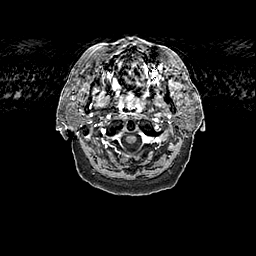

Glioma overlay -- Slice #2

[Home][Help][Clinical] Slice 2